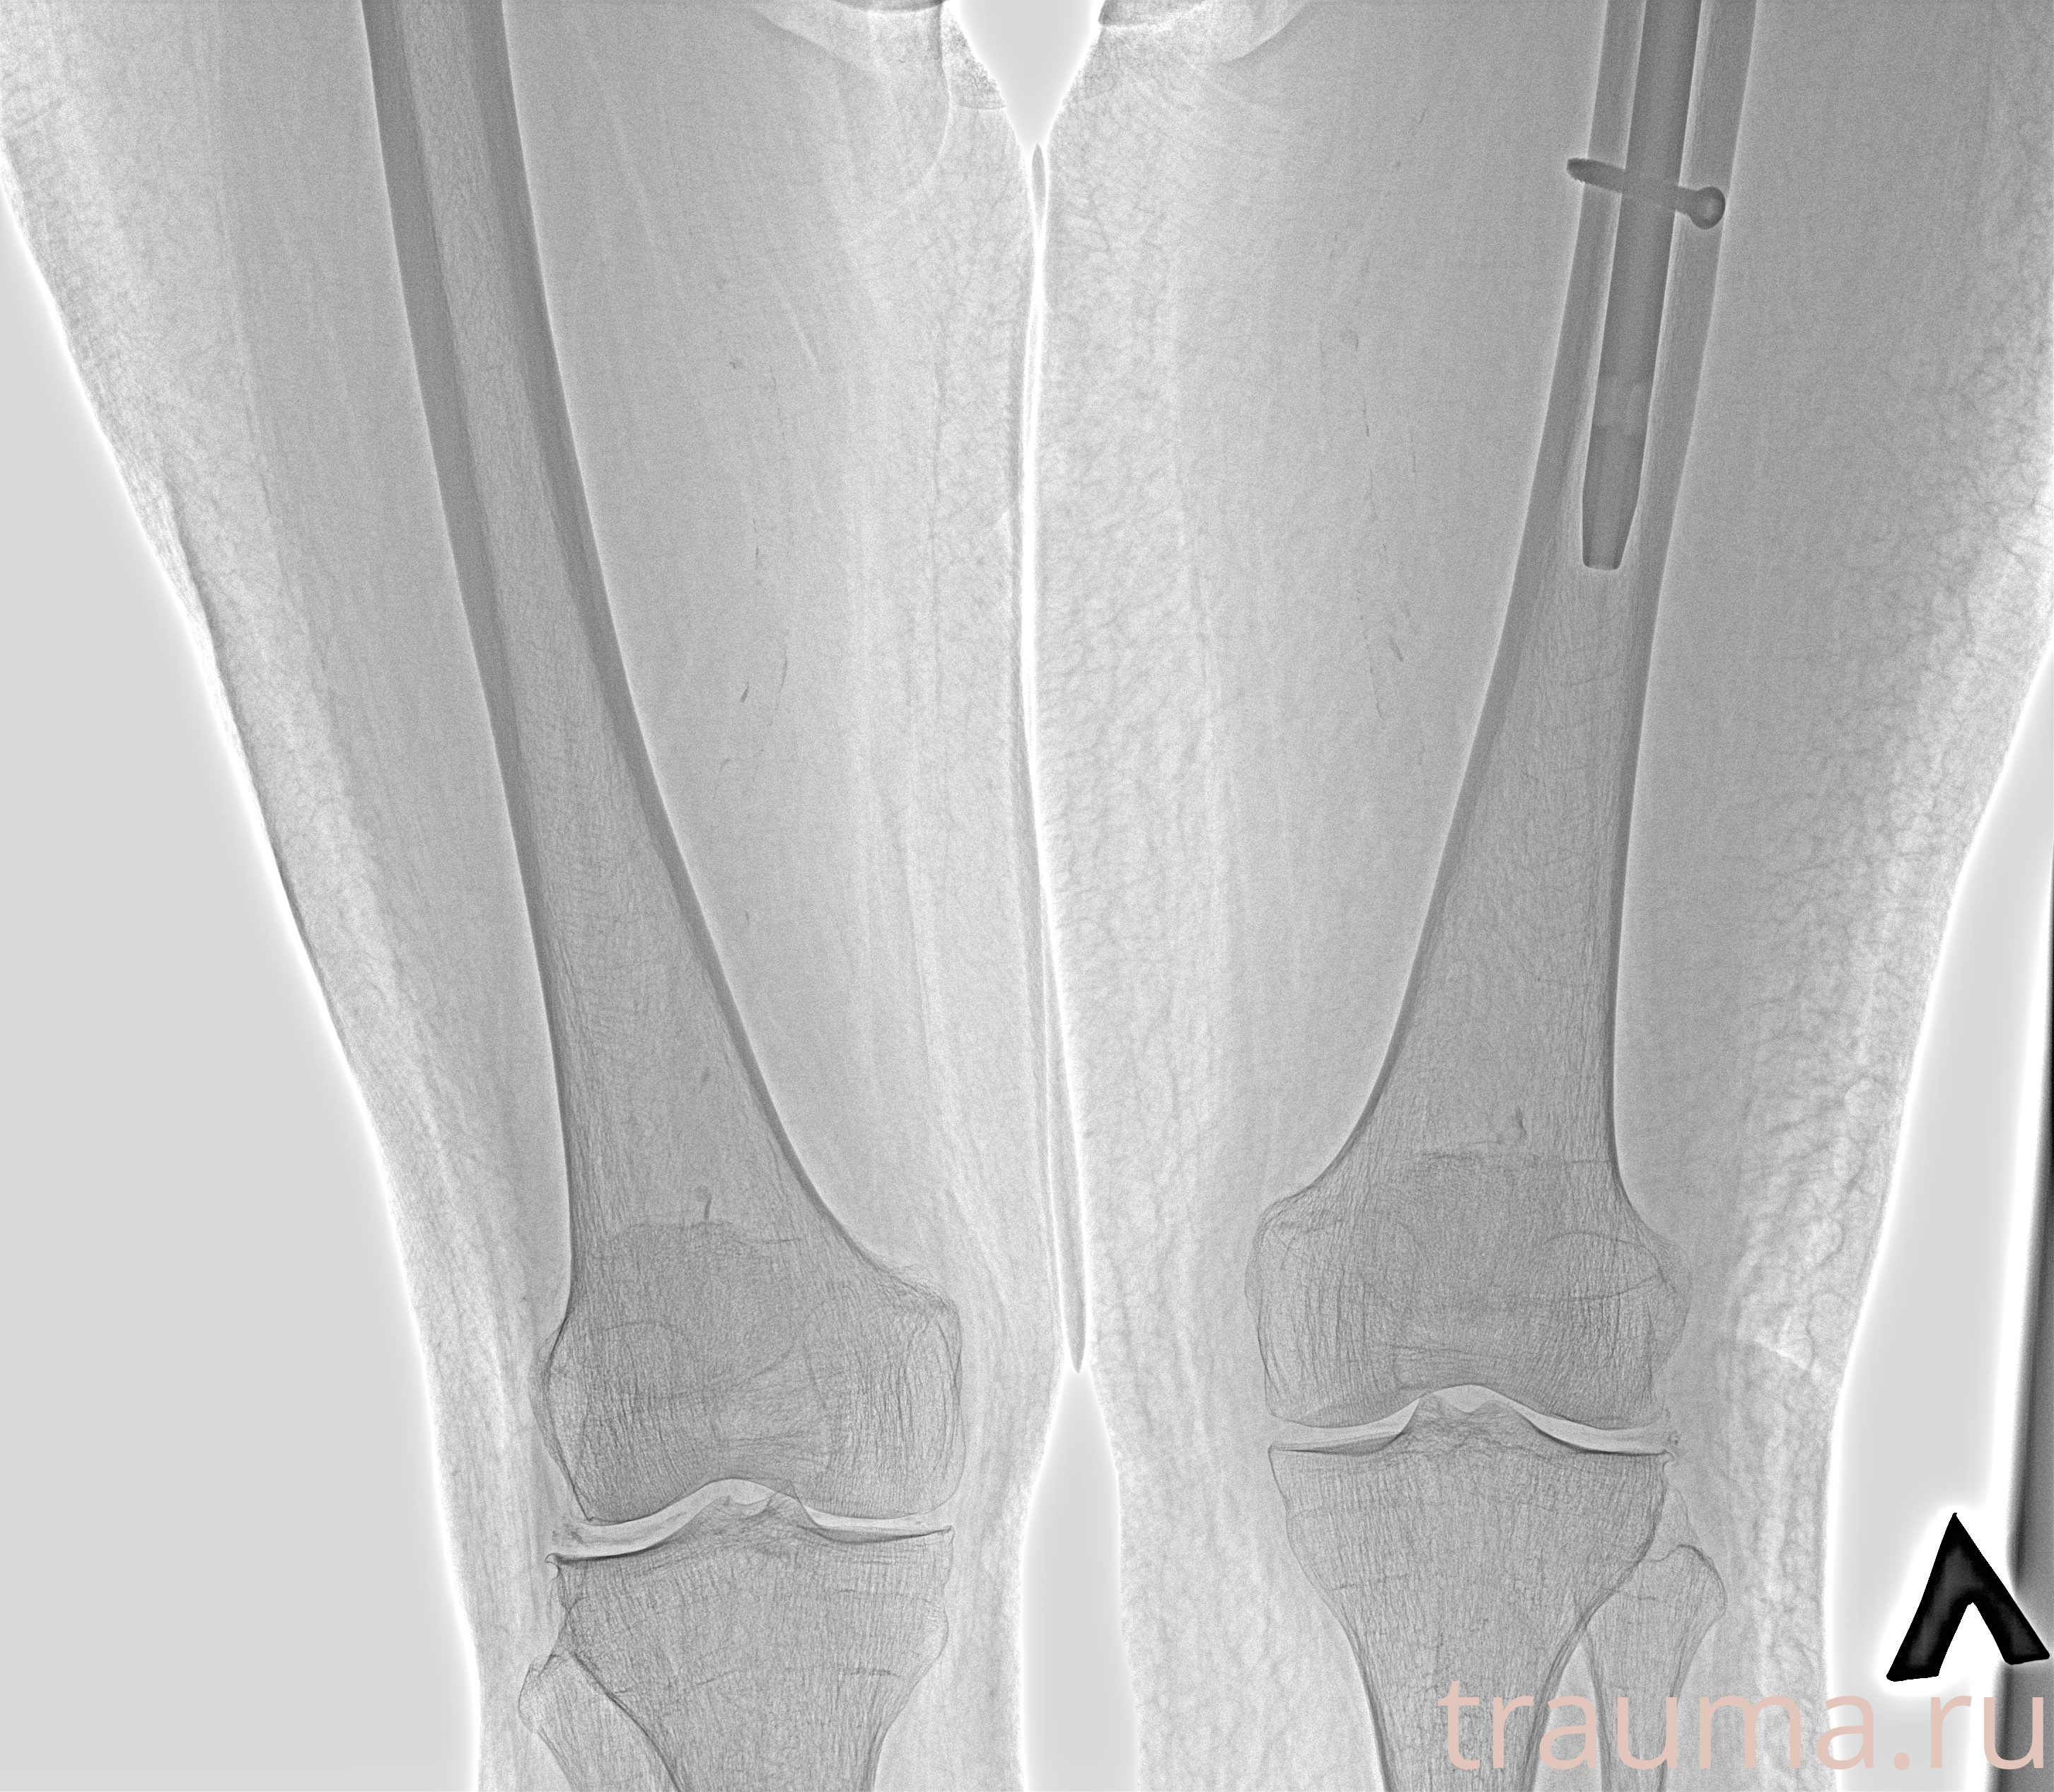

Рентгенограммы

Рентген на дому: по вашему адресу приезжает врач-рентгенолог, травматолог-ортопед с мобильным рентгеновским аппаратом, проводит диагностику травмы или заболевания, делает необходимые рентгенограммы, дает рекомендации по дальнейшему лечению. Получить качественные снимки в домашних условиях возможно благодаря уникальной методике, разработанной МосРентген Центром для института  Склифосовского